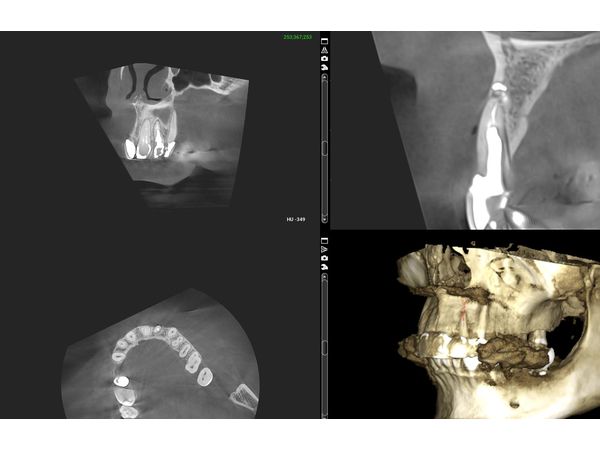

По результатам компьютерной томографии челюстей:

- атрофия и разрушение вестибулярной кортикальной пластинки;

- вертикальный перелом корня зуба.

По результатам повторной компьютерной номограммы, вестибулярная кортикальная пластинка и объём костной ткани восстановились. Пациентка ни на что не жаловалась. Внешний вид её полностью устроил.